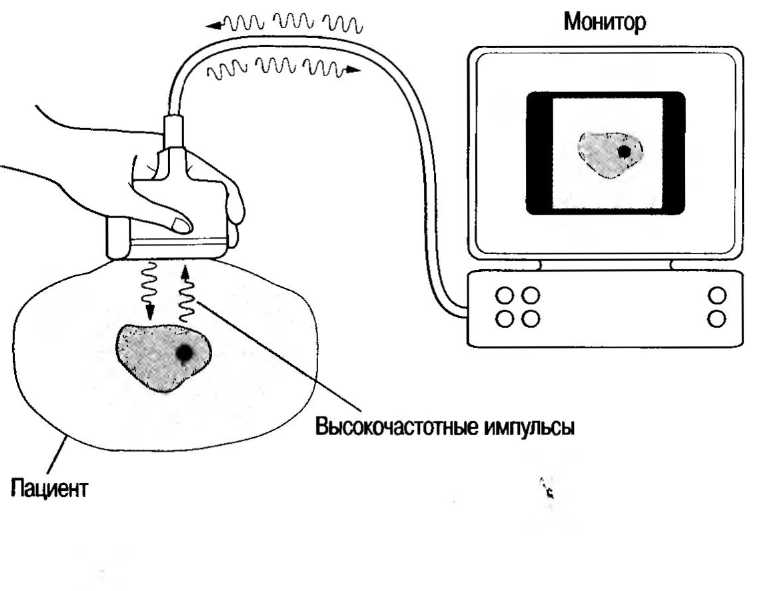

Ультразвуковой импульс, производимый сканером, который описан в данной главе, имеет частоту 2-10 МГц (1 МГц — это 1 000000 циклов/с). Продолжительность импульса составляет 1 микросекунду (одна миллионная часть секунды), импульсы повторяются с частотой 1000 в секунду. Различные ткани по-разному проводят ультразвук: некоторые ткани полностью отражают его, в то время как другие рассеивают сигналы, прежде чем они возвращаются к датчику. Волны проводятся через ткани с различной скоростью (например, 1540 м/с — это скорость распространения ультразвука в мягких тканях).

Отраженные ультразвуковые сигналы, воспринимаемые трансдьюсером, должны быть усилены в ультразвуковом аппарате. Отраженные сигналы от тканей, находящихся на большей глубине, затухают в большей степени, чем сигналы, отраженные от поверхностных тканей, поэтому первые должны усиливаться в большей степени. Ультразвуковые аппараты имеют устройство, изменяющее общую чувствительность, «порог» чувствительности аппарата, в той же степени, в какой происходит затухание отраженных зхосигналов с различной глубины. При работе с любым сканером необходимо добиваться сбалансированного изображения, с тем чтобы получать приблизительно равные по силе отражения от тканей на любой глубине.

При возвращениии отраженного эхо-сигнала к датчику становится возможной двухмерная реконструкция изображения всех тканей, через которые прошел ультразвуковой луч. Информация хранится в компьютере и воспроизводится на видео(телевизионном)-мониторе. Сильные отраженные сигналы называются высокоинтенсивными и выглядят на экране как яркие белые точки.

Ультразвуковые волны генерируются пьезоэлектрическими элементами датчика, который преобразует электрические сигналы в механические

(ультразвуковые) волны. Тот же датчик воспринимает отраженные сигналы и преобразует их назад в электрические сигналы. Датчики как передают, так и воспринимают ультразвук.